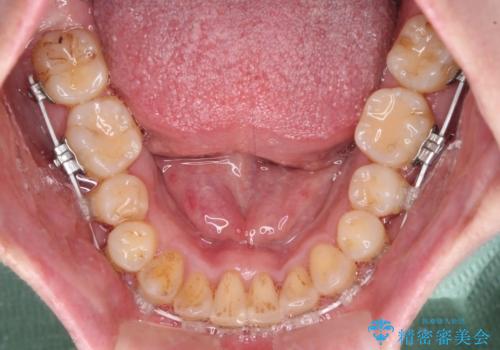

- 矯正装置

- 審美装置

舌の突出癖が強く、治療途中で上下前歯が乖離した開咬となってしまいました。

舌のトレーニングで開咬は改善できますが、なかなかトレーニングが進まず、治療期間は想定よりも長期化してしまいました。